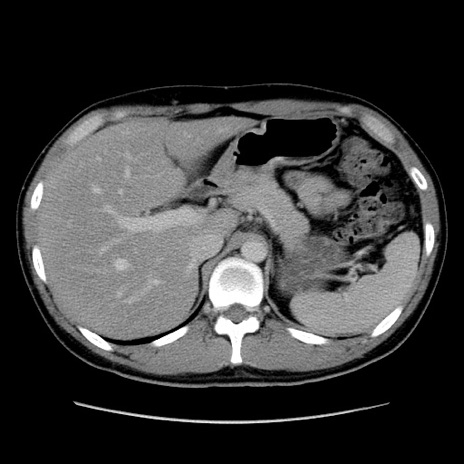

症例36(横断像)

【症例】20歳代 男性

【主訴】心窩部痛

【現病歴】今朝より上腹部痛あり。一旦軽快していたが再度出現したため救急要請。昨日夕に白身の魚を含む刺身を食べた。

【身体所見】BP 136/89mmHg、HR 74/min、BT 37.0℃、腹部:膨満、軟、心窩部に圧痛あり。反跳痛なし、筋性防御なし、腸雑音やや亢進あり。

【データ】WBC 17700、CRP 0.48